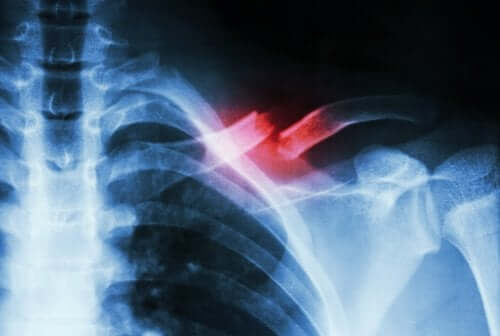

On parle de fracture de stress lorsqu’une petite fracture apparaît dans un os sans qu’elle ne soit le résultat d’un choc. Dans ce cas, la cause la plus fréquente est la réalisation de mouvements répétitifs ou une augmentation rapide de la quantité ou de l’intensité d’une activité.

Ce type de fracture n’est pas facile à diagnostiquer. Un examen spécialisé et complémentaire est nécessaire afin de ne pas le confondre avec d’autres pathologies. En effet, il est courant que de simples radiographies ne permettent pas de détecter la fracture.

Une fracture de stress est une sorte de fissure dans l’os. Elle se forme à la suite de microtraumatismes répétés ou d’une surcharge. Elle se manifeste principalement par une forte douleur qui apparaît lors des activités physiques et disparaît lorsqu’on les arrête.